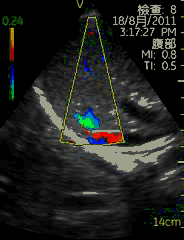

Vscan临床图片 腹部